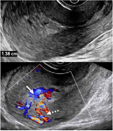

2.宫内妊娠的偏心着床(图2):指受精卵偏心着床于结构正常的子宫。正常妊娠的着床部位常靠近子宫中线,也偶可偏向左右侧,即偏心着床;此时,超声报告应提示为“宫内妊娠”或描述为“妊娠囊偏心着床但完全被子宫内膜包绕”,结论为“宫内妊娠”。该专家共识明确提出了应避免继续使用既往常用的‘宫角妊娠’‘宫角部妊娠’术语表述。

图2 宫内妊娠的偏心着床超声图像,妊娠囊位于偏心位置,但完全被子宫内膜包绕。图a为36岁孕妇(孕5周4天)经阴道超声横切面灰阶超声图,显示一偏离中线靠近左侧的妊娠囊(箭头所示)内含卵黄囊及胚胎。妊娠囊完全被子宫内膜包绕,可直接报告为“宫内妊娠”;也可补充描述为“妊娠囊偏心着床但完全被子宫内膜包绕”,但超声仍提示为“宫内妊娠”,以免与输卵管间质部异位妊娠混淆,避免使用‘宫角妊娠’或‘宫角部妊娠’等术语。图b为三维超声冠状面重建图,有助于确认妊娠囊位于子宫内膜内(图2译自参考文献[1])

考虑该专家共识对既往这一易混淆的临床问题提出明确的重新定义,是因为既往很长一段时间使用的‘宫角妊娠’,实际包含了“宫内妊娠的偏心着床”及“输卵管间质部异位妊娠”两种情况,短期超声随访或三维冠状面重建对两者的鉴别诊断较有帮助。